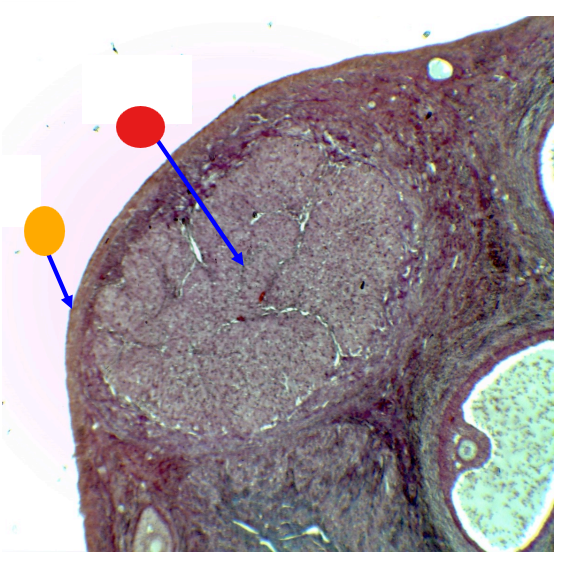

What is this

mature follicle

red

cumulus oophorus

orange

tertiary follicle

yellow

intermediate tertiary to mature follicle

red

corpus luteum

orange

tunica albuginea